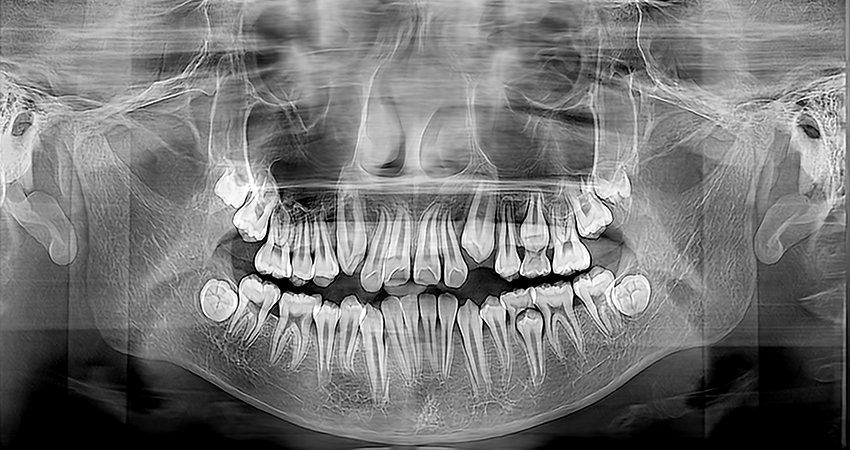

La máquina panorámica dental de Meyer proporciona a los dentistas imágenes panorámicas de alta calidad y vistas laterales, que pueden usarse para diagnosticar la dentición completa, la mandíbula y la articulación temporomandibular. También es adecuada para el diagnóstico de fracturas maxilofaciales y para el diseño de planes de ortodoncia.

Galería de imágenes